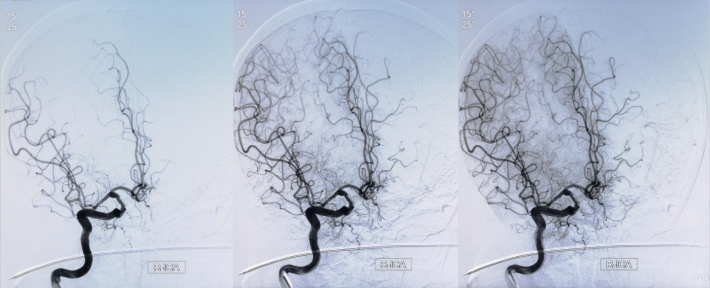

微导丝通过狭窄血管段

放置微导丝远端至左侧大脑中动脉上干M2段

3mm*15mm球囊扩张

球囊扩张后

✔术中要点:左侧颈内动脉虹吸段狭窄考虑为夹层,予反复多个角度导引导管造影,以明确真假血管腔,微导丝通过狭窄段血管时谨慎、轻柔操作,务必判断导丝应从真腔通过。先予球囊扩张,观察扩张后狭窄段血管管径恢复情况。释放前准确定位支架近端,远端,应完全覆盖狭窄血管段。